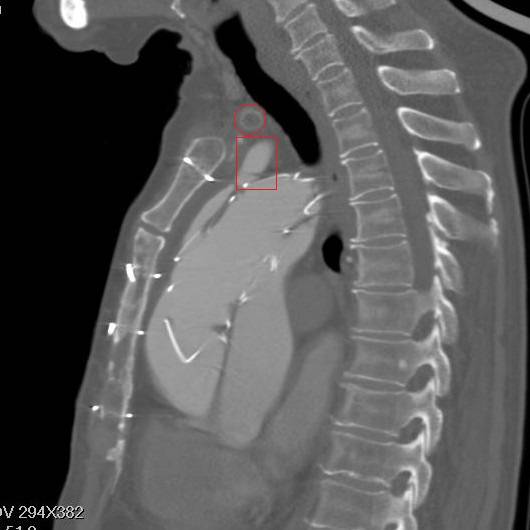

矢状面重建,胸骨钢丝很明显,方框示左颈总动脉,支架前端在假腔,后端在真腔。圆框示闭塞的人工血管

方框示左左锁骨下动脉,重度狭窄

细读其原手术记录,术式是杂交手术。于升主动脉内植入一枚覆膜支架,覆膜支架倒装,即植入前将覆膜支架从输送系统中拆出,前后颠倒,并预开窗。支架前端定位在第一内膜破口和冠脉开口之间,该例第一内膜破口和右冠开口有一定距离,作为前端锚定区。先作左锁骨下动脉—左颈总动脉—头臂干人工血管搭桥。支架后端定位在主动脉弓上,为达到良好后端锚定,但避免造成脑部缺血,故在弓上分支开口相对的支架部位剪除且覆膜作预开窗。如果预开窗对位效果不佳,只要左锁骨下动脉没有覆盖,还可通过预先做好的人工血管搭桥为脑部供血。支架从股动脉植入。